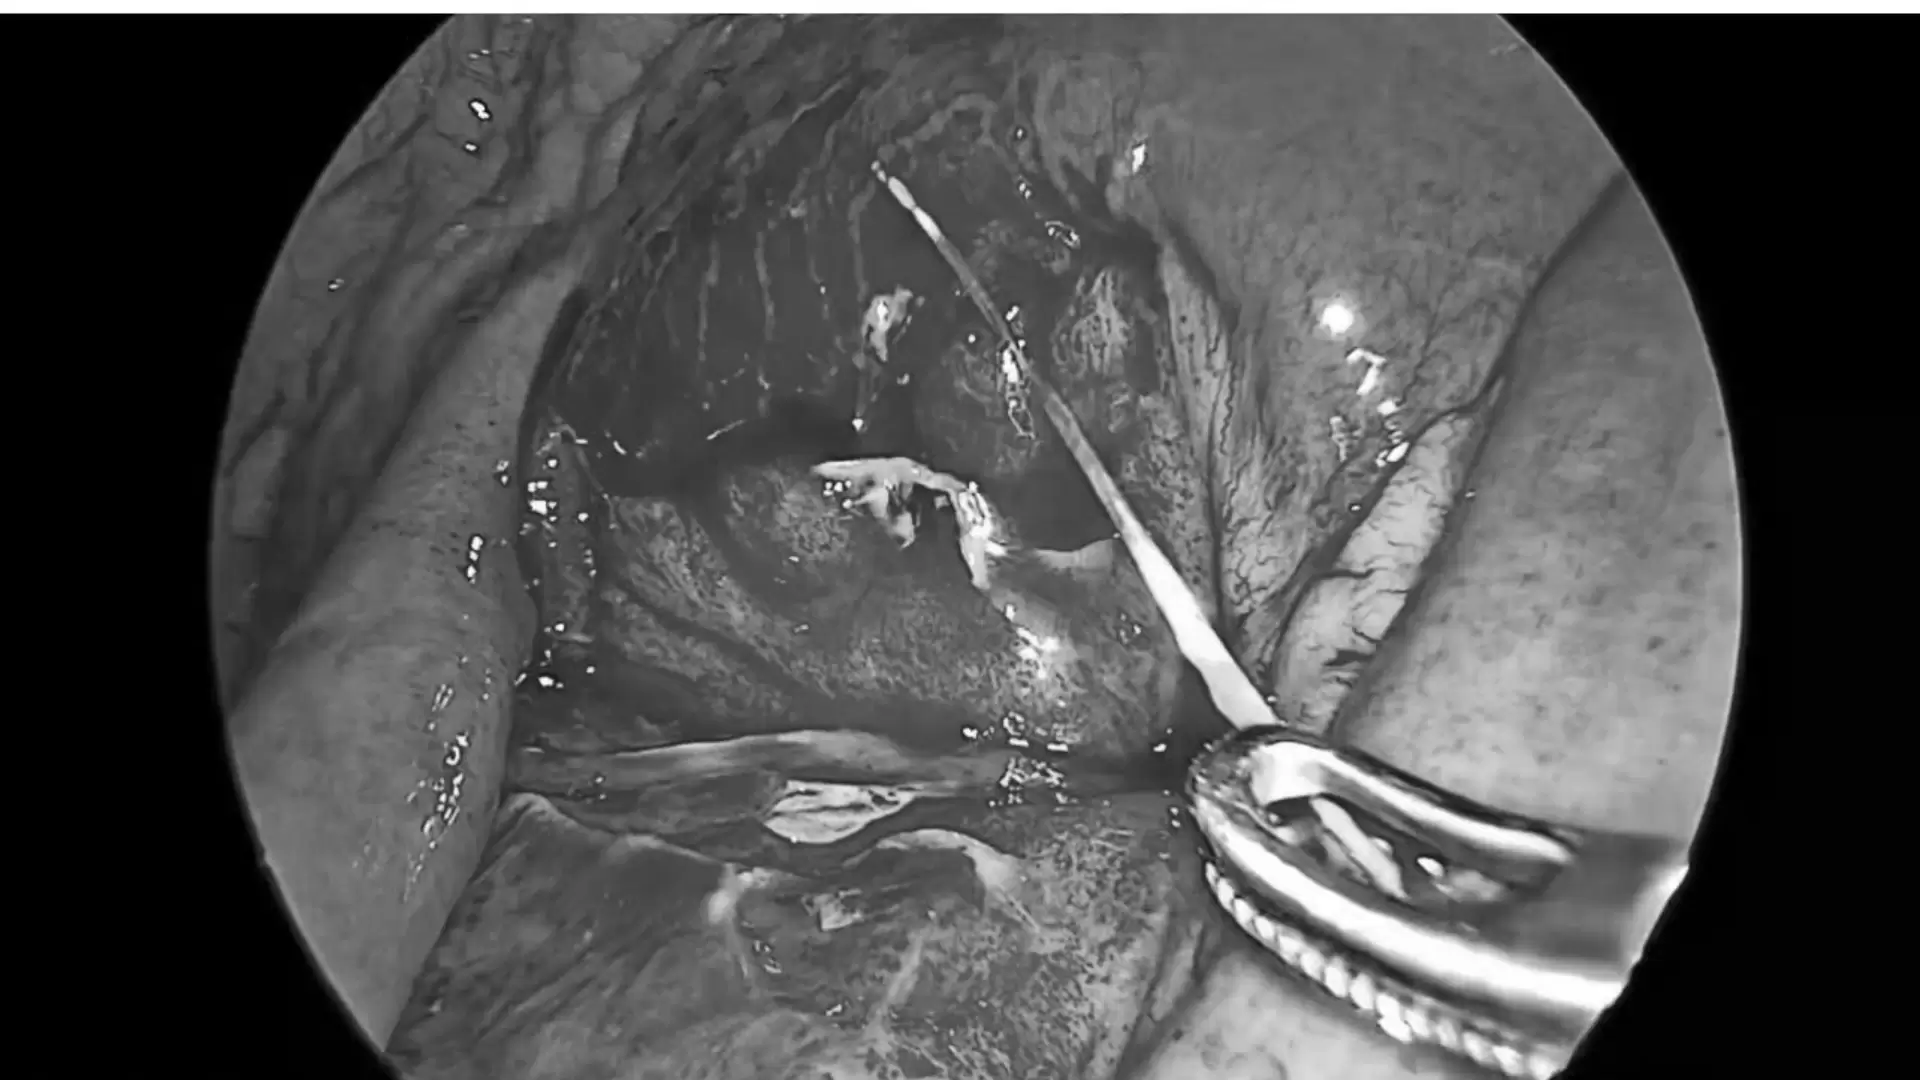

Ngay sau khi xác định chẩn đoán, bệnh nhân được chỉ định phẫu thuật cấp cứu. Ê-kíp phẫu thuật của Khoa Ngoại Tổng hợp đã tiến hành phẫu thuật nội soi lấy dị vật, xử trí lỗ thủng ruột và làm sạch ổ bụng.